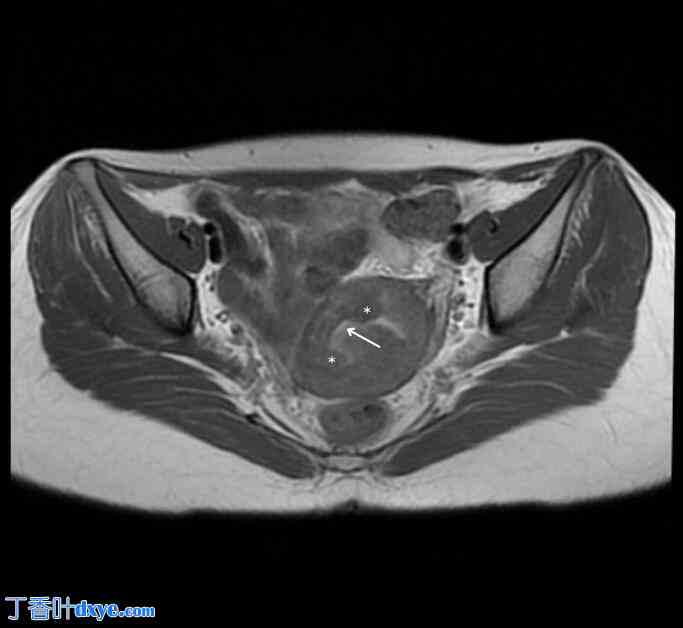

腹腔镜探查时,发现子宫体积增大,内有多个子宫肌瘤。前壁子宫肌瘤包括一个 4 x 4 厘米的壁内 FIGO 3 型子宫肌瘤和一个 3 x 2 厘米的 5 型子宫肌瘤,位于左侧输卵管附近。此外,在子宫前后壁上均发现多个小的幼苗状病变。这些病变与可能在先前宫腔镜子宫肌瘤切除术后出现的寄生性子宫肌瘤相符。对这些病变进行了活检,然后切除并电灼治疗。组织病理学证实这些病变为良性平滑肌瘤(寄生性子宫肌瘤)(图 3、图 4)。

寄生性子宫肌瘤的组织病理学切片显示子宫平滑肌瘤的特征性特征,无异形性或明显的有丝分裂活动。